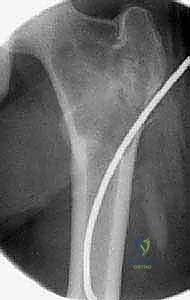

في الـ ABC، تظهر الآفة غير مركزية، متمددة، وتدفع قشرة العظم للخارج لتصبح رقيقة جداً مثل "قشرة البيضة".

تُظهر هذه الأشعة السينية كيس عظم متمدد (ABC). لاحظ التوسع الكبير في العظم وترقق القشرة العظمية مقارنة بالكيس أحادي الغرفة.